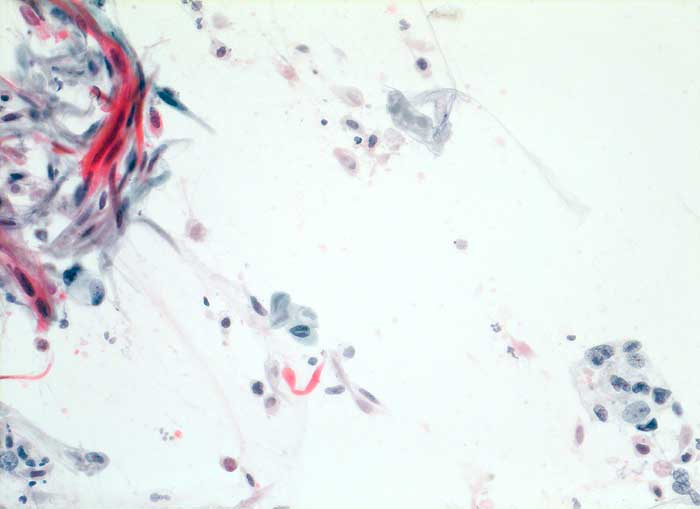

Verhornende Plattenepithelkarzinome sind charakterisiert durch mehr einzeln gelagerte Zellen mit deutlicher Pleomorphie, das Zytoplasma ist dicht und orangeophil. Die Kerne sind pyknotisch oder erinnern an Lavabrocken.

Die Abbildungen zeigen ein verhorntes und ein unverhorntes Plattenepithelkarzinom zum Vergleich.